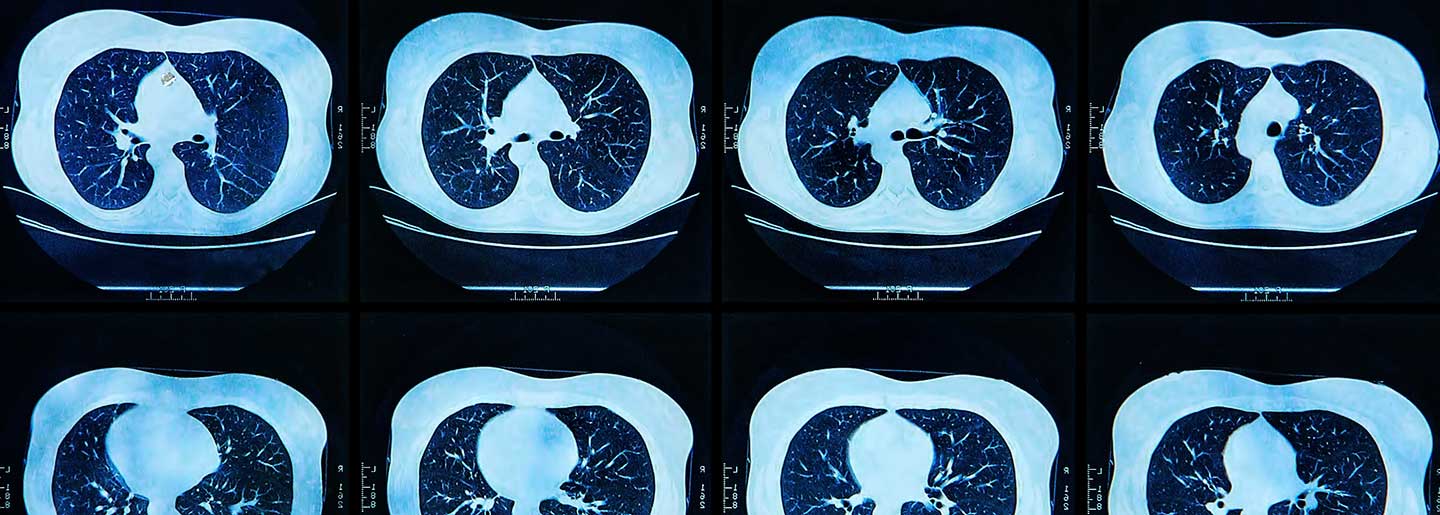

Moffitt researchers wanted to take advantage of the capabilities of computer deep learning to develop a new framework to measure PD-L1 biomarker levels in NSCLC patients in a non-invasive manner. They chose to use features of PET/CT scan images, such as shape, size, pixel intensity and textures to train computers to measure PD-L1 expression. They developed a deep learning score to predict PD-L1 expression, and after validation through different patient cohorts were able to use their model to predict checkpoint inhibitor outcomes in NSCLC patients.

“This study is important, as it is the single largest multi-institutional radiomic study population of NSCLC patients to date treated with immunotherapy to predict PD-L1 status and subsequent treatment response using PET/CT scans,” said Robert Gillies, Ph.D., chair of the Department of Cancer Physiology at Moffitt. “Because images are routinely obtained and are not subject to sampling bias per se, we propose that the individualized risk assessment information provided by these analyses may be useful as a future clinical decision support tool pending larger prospective trials.”